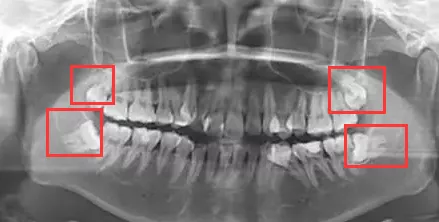

有些智齿会“趴在”邻牙上 , 容易积存食物 , 导致邻牙蛀牙甚至邻牙牙冠部分被吸收 。

阻生齿:

阻生齿通常长在牙槽骨里 , 冒不出来 。 如果它动不动就发炎疼痛或有牙病 , 就要尽快拔掉 。